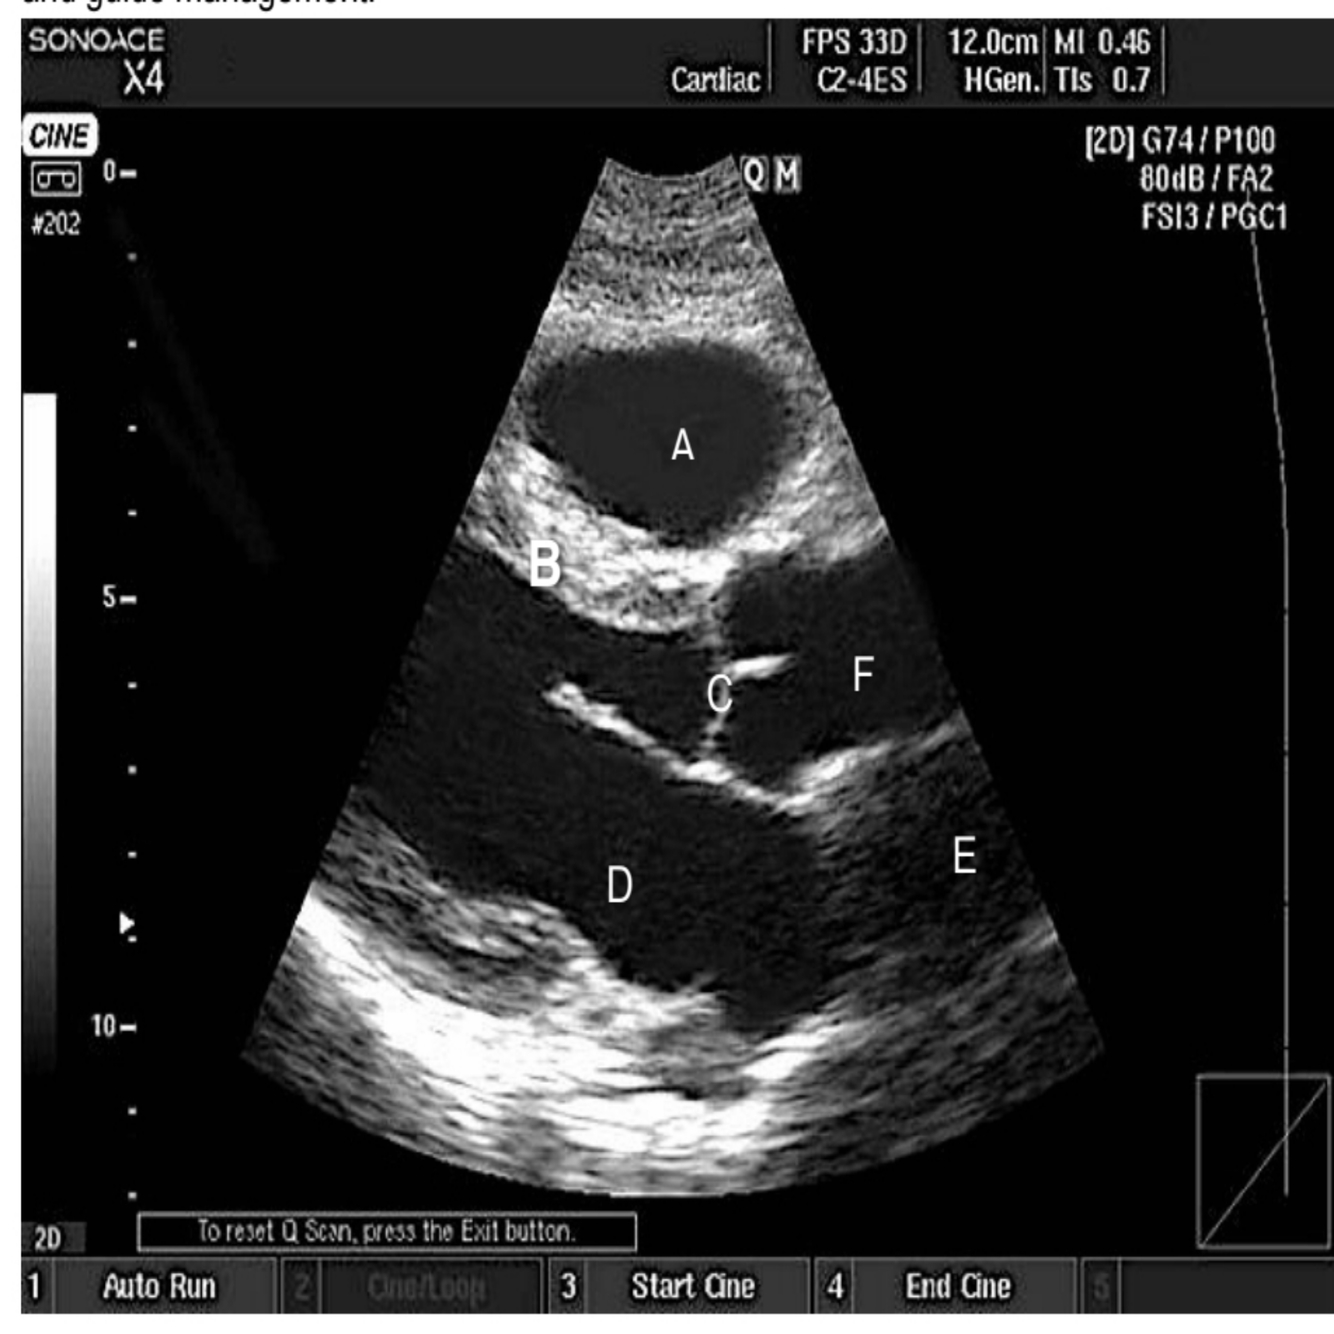

A patient in ICU is hypotensive. You decide to use the transthoracic echo to investigate the cause

and guide management.

a) Name the specific view.

b) Label from A to F.

c) What measurement can you obtain from the above view that is needed in the calculation of cardiac output?

d) Using the given measurements, Aorta diameter 2 cm; VTI 14 cm; EF 68%; heart rate 51 beats per minute supply the formula and calculate cardiac output. (5)

A

a) Parasternal long axis view

b) a= RV b= IVS C= AV D=LV E= RA F= Ascending aorta

c) VTI of LV, LVOT diameter = radius